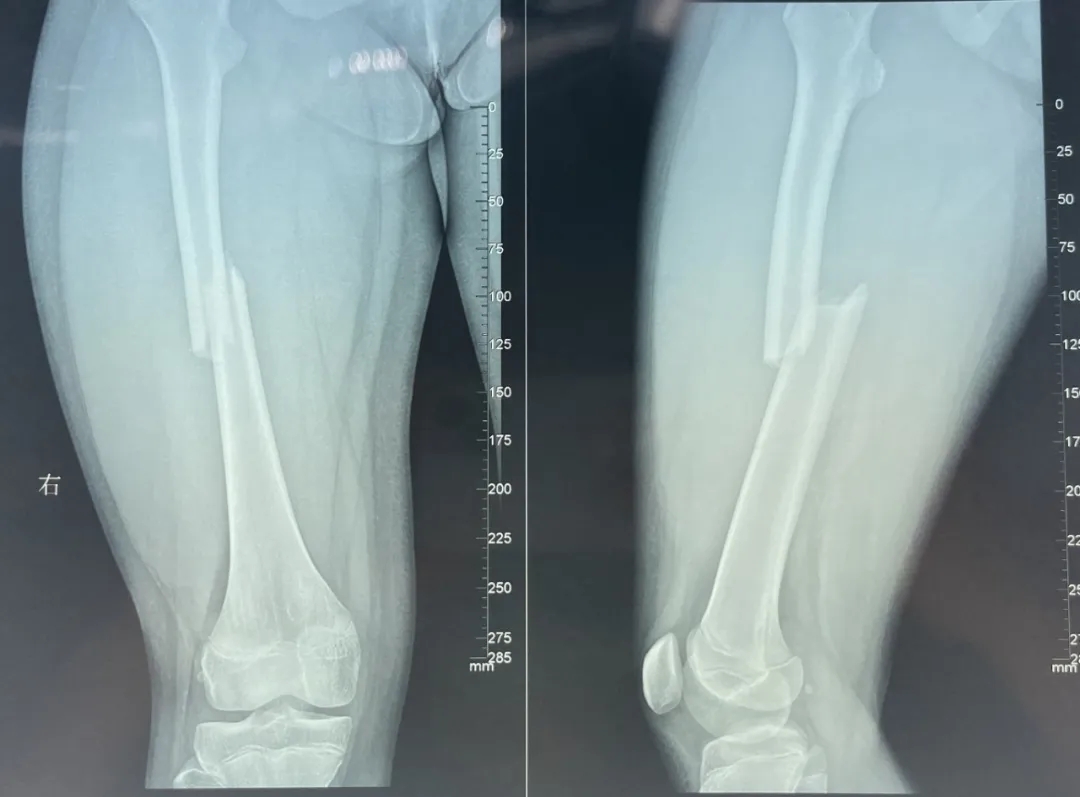

樂樂(化名)是一名小學(xué)生,前兩天上體育課在短跑跨欄時(shí)不慎摔倒傷及右大腿,當(dāng)時(shí)腿部疼痛難忍,腫脹明顯,活動(dòng)受限且畸形,家人獲悉后立即送其到我院急診醫(yī)學(xué)科治療。經(jīng)診斷,樂樂是右股骨干骨折,入住我院骨科脊柱創(chuàng)傷組。

經(jīng)與家長(zhǎng)詳細(xì)溝通,我院骨科專家團(tuán)隊(duì)決定為患兒實(shí)施右股骨干骨折閉合復(fù)位彈性髓內(nèi)釘內(nèi)固定手術(shù)。術(shù)中,顧署光主任及趙飛副主任醫(yī)師在團(tuán)隊(duì)專家及手術(shù)室、麻醉科醫(yī)護(hù)人員的配合下,憑借精湛的醫(yī)術(shù)與熟練的操作手法,在樂樂患肢內(nèi)外兩側(cè)開了2個(gè)不足2cm小切口,對(duì)稱插入兩根彈性髓內(nèi)針,利用鈦合金或不銹鋼良好的彈性恢復(fù)力作用于骨骼,通過髓腔的3個(gè)接觸點(diǎn)轉(zhuǎn)換成推力和壓力,從而使骨折復(fù)位。手術(shù)成功,目前樂樂恢復(fù)良好。

顧署光主任介紹,彈性髓內(nèi)釘內(nèi)固定技術(shù)被稱為兒童骨科界的一次革命,該項(xiàng)技術(shù)利用多點(diǎn)固定的原理,微創(chuàng)、有效地治療四肢骨折的患兒,是目前兒童長(zhǎng)骨干骨折治療中的主流技術(shù)。該項(xiàng)技術(shù)損傷小,手術(shù)時(shí)間短,無(wú)明顯的手術(shù)疤痕,骨折愈合快,康復(fù)效果佳,對(duì)患兒及家屬心理影響小。主要適用于3歲至15歲兒童股骨干骨折,4歲以上兒童尺橈骨雙骨折,兒童脛腓骨骨折,兒童肱骨干骨折等。